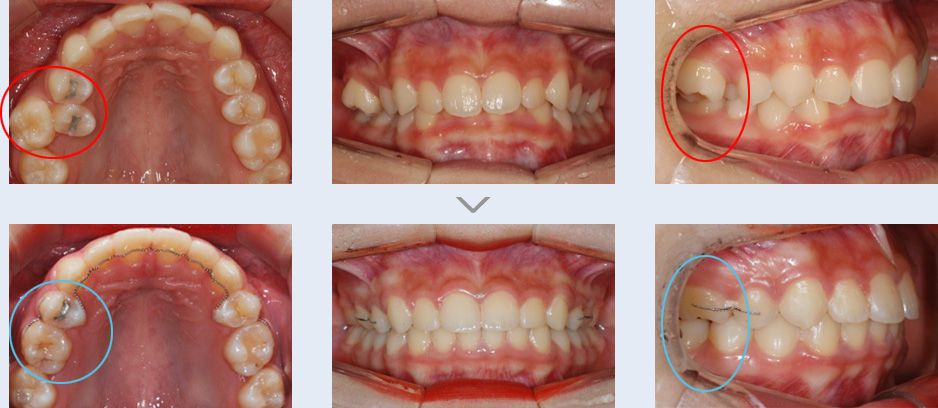

왼쪽 위 치아들의 모양과 위치가 정상적이지 않았고 치열이 대칭적이지 않아 교정 치료를 권유 받고 내원한

학생입니다. 좌측 위 송곳니와 작은 어금니의 위치가 바뀌어 있고 우측 작은 어금니가 결손되어 주위 치아들이

기울어져 있으며 틈새가 벌어져 있습니다. 고정식 교정 장치를 이용하여 치열을 고르게 하고 결손된 치아 공간을

재배치하였습니다.

비대칭 모양의 치열을 대칭 형태로 개선하였고 송곳니와 작은 어금니의 위치를 정상적으로 되돌렸습니다. 또한

결손된 치아 위치는 성인이 된 후 임플란트를 식립할 수 있도록 유지 관리하였습니다.